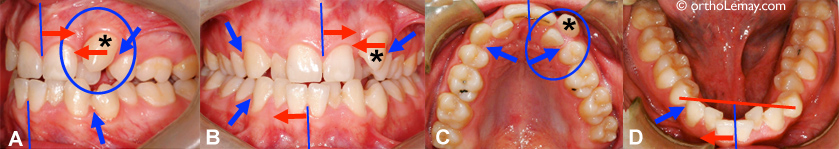

Exemple de la fermeture d’un diastème entre des incisives centrales supérieures à la suite de l’éruption des canines permanentes. (A) À l’âge de 8.9 ans, ce garçon présente un diastème important et un frein labial qui s’attache entre les incisives centrales. (B) Près de 5 ans plus tard (13.5 ans), les canines permanentes sont sorties et ont contribué à fermer le diastème en déplaçant les incisives vers le centre. Aucune frénectomie n’a été faite.